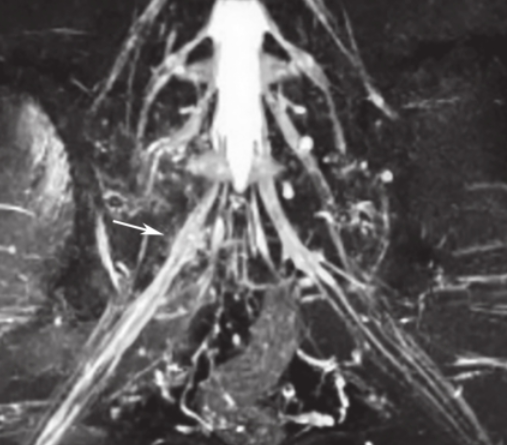

白靖平等认为用MRI扫描骶骨斜冠状面,当有骶神经损伤时,MRI图像显示骶神经周围脂肪组织消失,其直径变窄,且神经走向改变等。许道洲等则认为MRI平扫不能直接显示骶神经根的损伤,MRISPACE-STIR序列扫描能提供三维TSE对比成像。在SPACE-STIR序列扫描图像上,在骨折周围出现下列征象时应考虑有神经根的损伤:

①神经节后线状高信号走行中断,是诊断神经根损伤的直接征象,表现为神经根在骨折处呈截断征,如图14;

图14斜冠状面SPACE-STIR序列MRI神经成像重建可见右侧S1神经中断(箭头所指),对侧显示良好